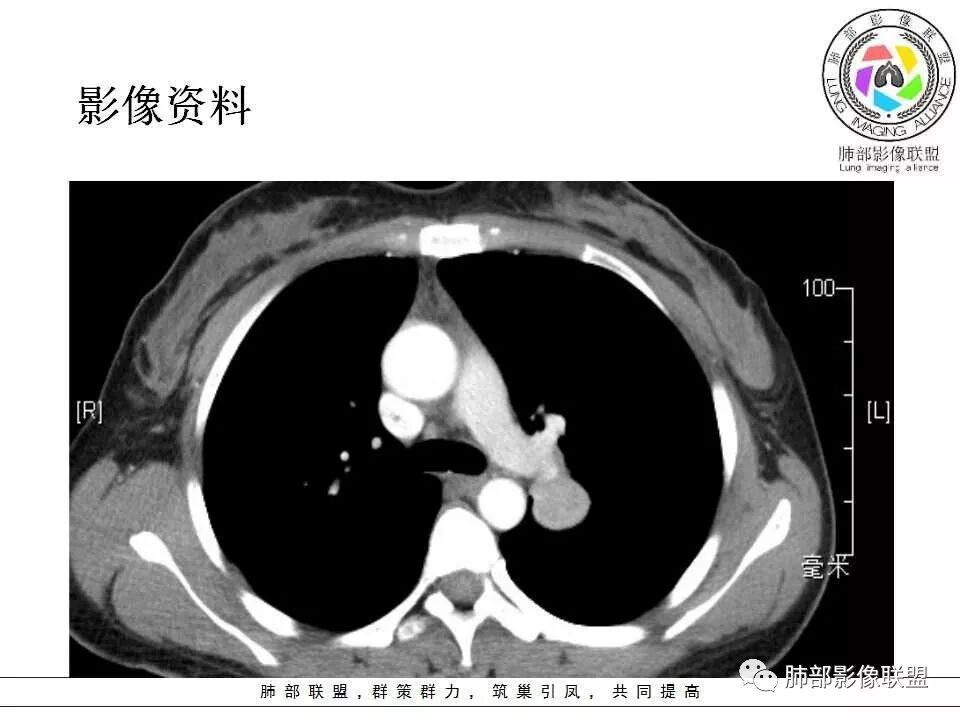

左肺门肿块,边缘光滑清晰,血管贴边,明显均匀强化,考虑PSP,鉴别类癌。

学习一下南大的诊断思路,左肺门区病灶,应该没跨叶,感觉都在上叶,强化密度均匀,边缘清晰,与支气管关系不大,常规考虑良性病变,PSP可能性大,鉴别CD,血管源性。但是一年增大怎么解释,不知道增大多少。

左肺病灶与支气管关系密切,类癌粘膜下生长,支气管略变窄,支气管外病变较大,符合冰山征表现,一年内有增长,考虑类癌,鉴别PSP,建议薄层重建。

我怎么又感觉跨叶间裂了,而且有胸膜尾征和可疑的指状突起,强化很明显,考虑SFT可能大,鉴别类癌和CD

年轻女性,左肺门区肿块,边缘光整,随诊有增大,恶性可能,类癌?鉴别psp、CD。

患者中年女性,发现左肺上叶占位,随访发现体积增大。胸部CT:左肺上叶尖后段实性占位,位于支气管旁,未见支气管阻塞,病灶边界清楚,边缘光滑,增强可见病灶均匀强化,血管贴边,考虑良性病变,PSP?

左肺上叶后段紧贴斜裂结节影,支气管通畅,斜裂无移位,说明病灶来源斜裂可能,强化密度均匀,边缘清晰,考虑良性病变,PSP可能性大,鉴别CD。

青年女性,慢性病程,实验室指标末提及,左肺门区肿块,边缘光滑,无明显分叶,周围清晰,增强明显强化,血管贴边,复查有增大,考虑良性或低度恶性病变,PSP?

患者中年女性,发现左肺上叶占位1年余入院,随访发现体积增大。胸部CT:左肺上叶尖后段近肺门及叶间裂实性类圆形结节,病灶边界清楚光滑,增强可见病灶明显均匀强化,其旁未见支气管堵塞。综合考虑良性病变,孤立性纤维瘤可能,鉴别巨大淋巴结增生症及硬化性肺细胞瘤。

青年女性,左肺门占位,边缘光滑,强化均匀,考虑为良性病变,PSP可能,近期复查增大,不除外恶性病变。

年轻女性,体检发现,左肺上叶近肺门处结节,边缘光滑,均匀明显强化,血管贴边,支气管无关,考虑PSP。

中年女性,发现左肺上叶占位。胸部CT:左肺上叶尖后段孤立卵圆形实性病灶,位于支气管旁,边界清楚,边缘光滑,血管贴边,肺动脉为主征,增强扫描明显均匀强化。考虑:PSP?鉴别CD、类Ca。

青年女性,左肺门占位。定位:跨叶间裂,下叶邻近支气管推压,考虑肺外病变。影像表现:血管贴边,边缘光滑,强化均匀,考虑良性病变,PSP可能大,鉴别CD。

左肺上叶类圆形实性病灶,边缘光滑,可见血管贴边征,病灶与左肺上叶支气管关系密切,左肺动脉相对增粗,增强病灶均匀强化,常规考虑PSP,其次神经内分泌肿瘤不排除。

厚层,只有动脉期。左肺门占位,边界清,动脉期强化比较明显,后段支气管不明确,考虑恶性,类癌可能。psp渐进性强化,动脉期好像没这么明显。

年轻女性,左肺门肿块,边缘光滑,密度较均匀,增强后肿块明显均匀强化,血供丰富,病史提示一年明显增大,也说明富血供,常规考虑PSP,类癌待排。

年轻女性,边缘光滑圆形肿块,均匀强化,血管贴边儿,常规考虑硬化性肺细胞瘤(PSP)。不放心的地方就是幻灯第22幅,似乎有一个小尾巴。巨淋巴结增生症(CD)及类癌待排。CD这个部位可以,但是相对少见的多。类癌的话强化可以,但是形态太规整了,似乎也不符合。潘老师还说过一个糖瘤,忘记长啥样儿了。

中年女性,查体发现,偶有咳嗽,左肺上叶近肺门肿块,边缘光滑,密度均匀,有强化,与支气管关系不清,有血管贴边,随访有增大,还是先考虑低度恶性肿瘤,类癌可能,鉴别psp。

青年女性,一年前发现肺结节,复查有增大,未见近期片对比,定位:左肺上叶左肺门旁见实性类圆形结节,边界清晰光整,有部分分叶征,增强有均匀强化,与左上叶后段支气管关系不好判断,左上叶后段支气管未显示,堵塞?狭窄?需冠矢状面看看,定性:常规考虑良性或低度恶性肿瘤,典型的类癌或硬化性肺细胞瘤psp可能,神经源性或神经内分泌肿瘤、巨淋巴结增生症CD不除外,转移瘤、孤立性纤维瘤待排,建议HRCT或支气管镜检查。

年轻女性,左肺门区占位,斜裂推移未跨叶,类圆形,增强扫描明显强化,和支气管关系显示不是太清楚,感觉关系不是太密切,未见阻塞性炎症,一年后有长大,首先考虑PSP,鉴别类癌,SFT。

左肺门区肿块,形态规则,边缘光滑,密度均匀,未见支气管截断,增强后均匀强化,血管似有贴边,年轻女性,考虑PSP,鉴别:CD,副节瘤。

36岁女性,发现左肺占位1年,时有干咳。CT:左肺门(上叶尖后段?)类圆形结节,边界清,靠前边缘似有GG0,近肺门侧与血管密切接触,似有小凸起,增强见明显均匀强化,似有条片状影往肺门侧血管钻。图片有点少,病灶与支气管的关系看不清(目前的图片与支气管不密切)。随诊结节增大,整体考虑典型类癌可能性大,鉴别硬化性肺细胞瘤。